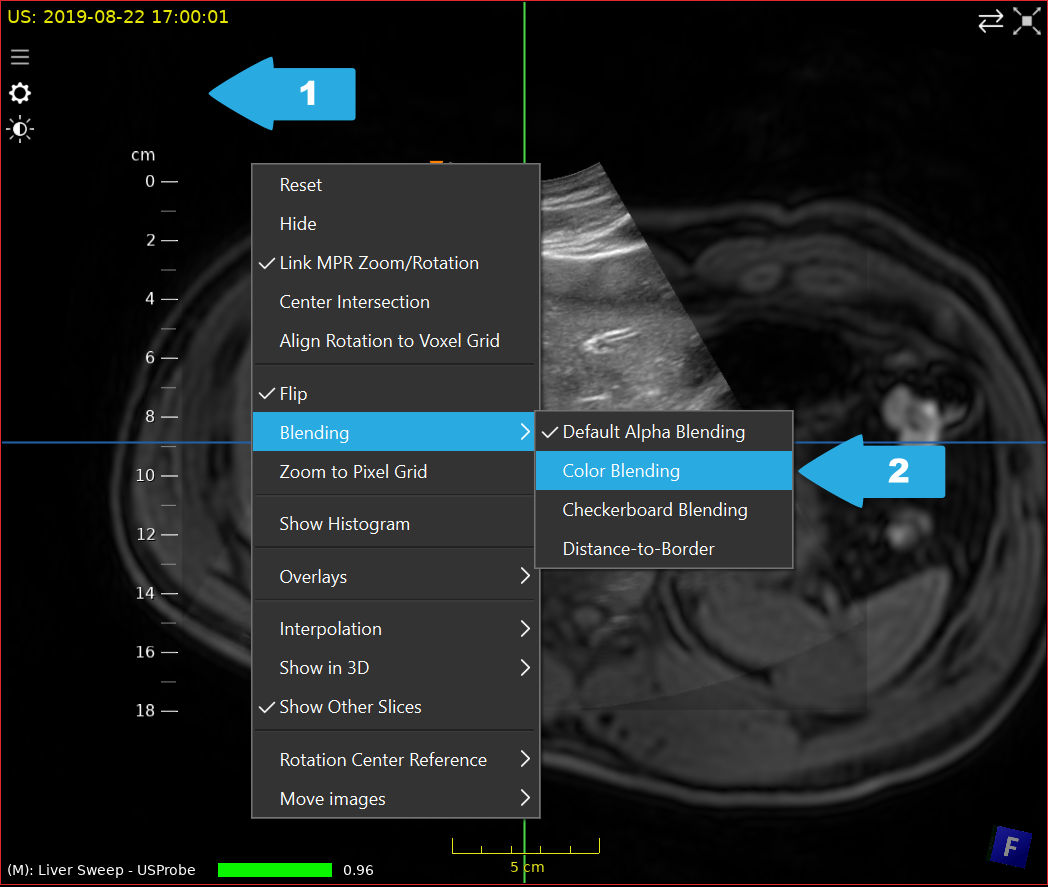

Furthermore, we can activate Color Blending for improved visualization by clicking on an empty space in a view (1) and selecting Blending > Color Blending (2).

../../_images/US.UltrasoundRegistrationTutorial.analysis02.png

Activation of color blending.